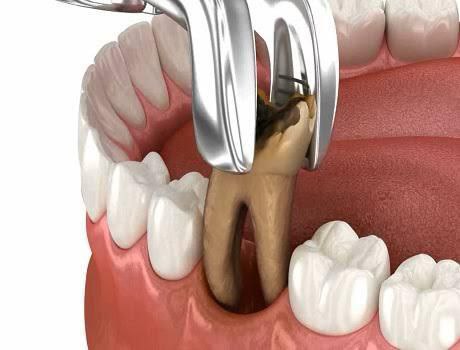

الخلع الجراحي للأسنان

إزالة الأسنان المكسورة أو المدفونة تحت اللثة، مثل ضروس العقل.

يعد خلع الأسنان، أو قلع الأسنان، جانبًا مهمًا من العناية بالأسنان عندما يتضرر أحد الأسنان بشكل كبير، إما بسبب العدوى الناتجة عن تسوس الأسنان أو الصدمة الناجمة عن طرق أو نتوء. في Kidz Smile، يجمع نهجنا في علاج الأسنان الخارجية بين الخبرة والتعاطف، مما يضمن حصول كل طفل على أفضل رعاية ممكنة مصممة خصيصًا لتلبية احتياجاته الخاصة.

- استكشاف البدائل: في حين أنه قد يوصى بخلع الأسنان في حالات الضرر الشديد، فإن فريقنا يستكشف علاجات بديلة كلما أمكن ذلك. وقد يشمل ذلك الإجراءات الترميمية، مثل تيجان الأسنان أو حشواتها، للحفاظ على بنية الأسنان الطبيعية.